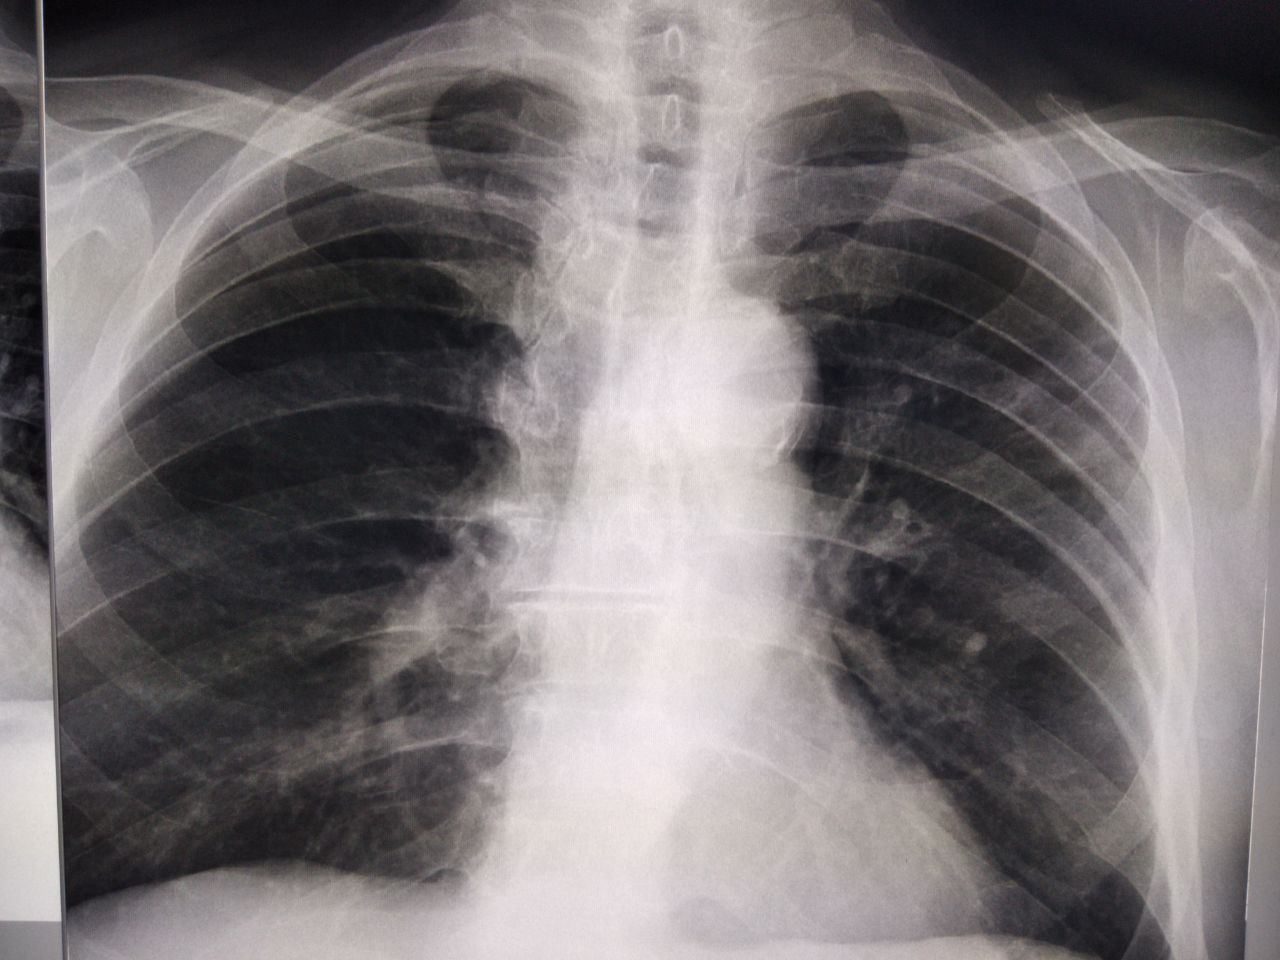

Как можно описать снимок

M

Срочно, кто разбирается в детских снимках? Ни анамнеза, ни архива, только снимки и направление

NL

Здравствуйте. Анамнез. Клиника

NL

Срочно, кто разбирается в детских снимках? Ни анамнеза, ни архива, только снимки и направление